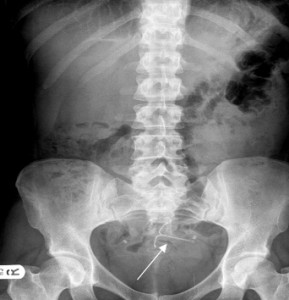

The most common side complication associated with the Mirena IUD is its tendency to move inside the uterus. This is known as intrauterine migration, and can result in the device becoming embedded in the uterine wall. If the IUD perforates the uterus, it can damage internal organs, causing abscesses, peritonitis and infection.

Some studies have shown that the Mirena IUD can migrate into the abdomen, which makes it incredibly difficult for physicians to find. The danger is that migration can go undetected, and a patient may be misdiagnosed as having simply expelled the device. It’s also been shown that the risk of uterine perforation is greater in women who have delivered a child within the last 6 months.